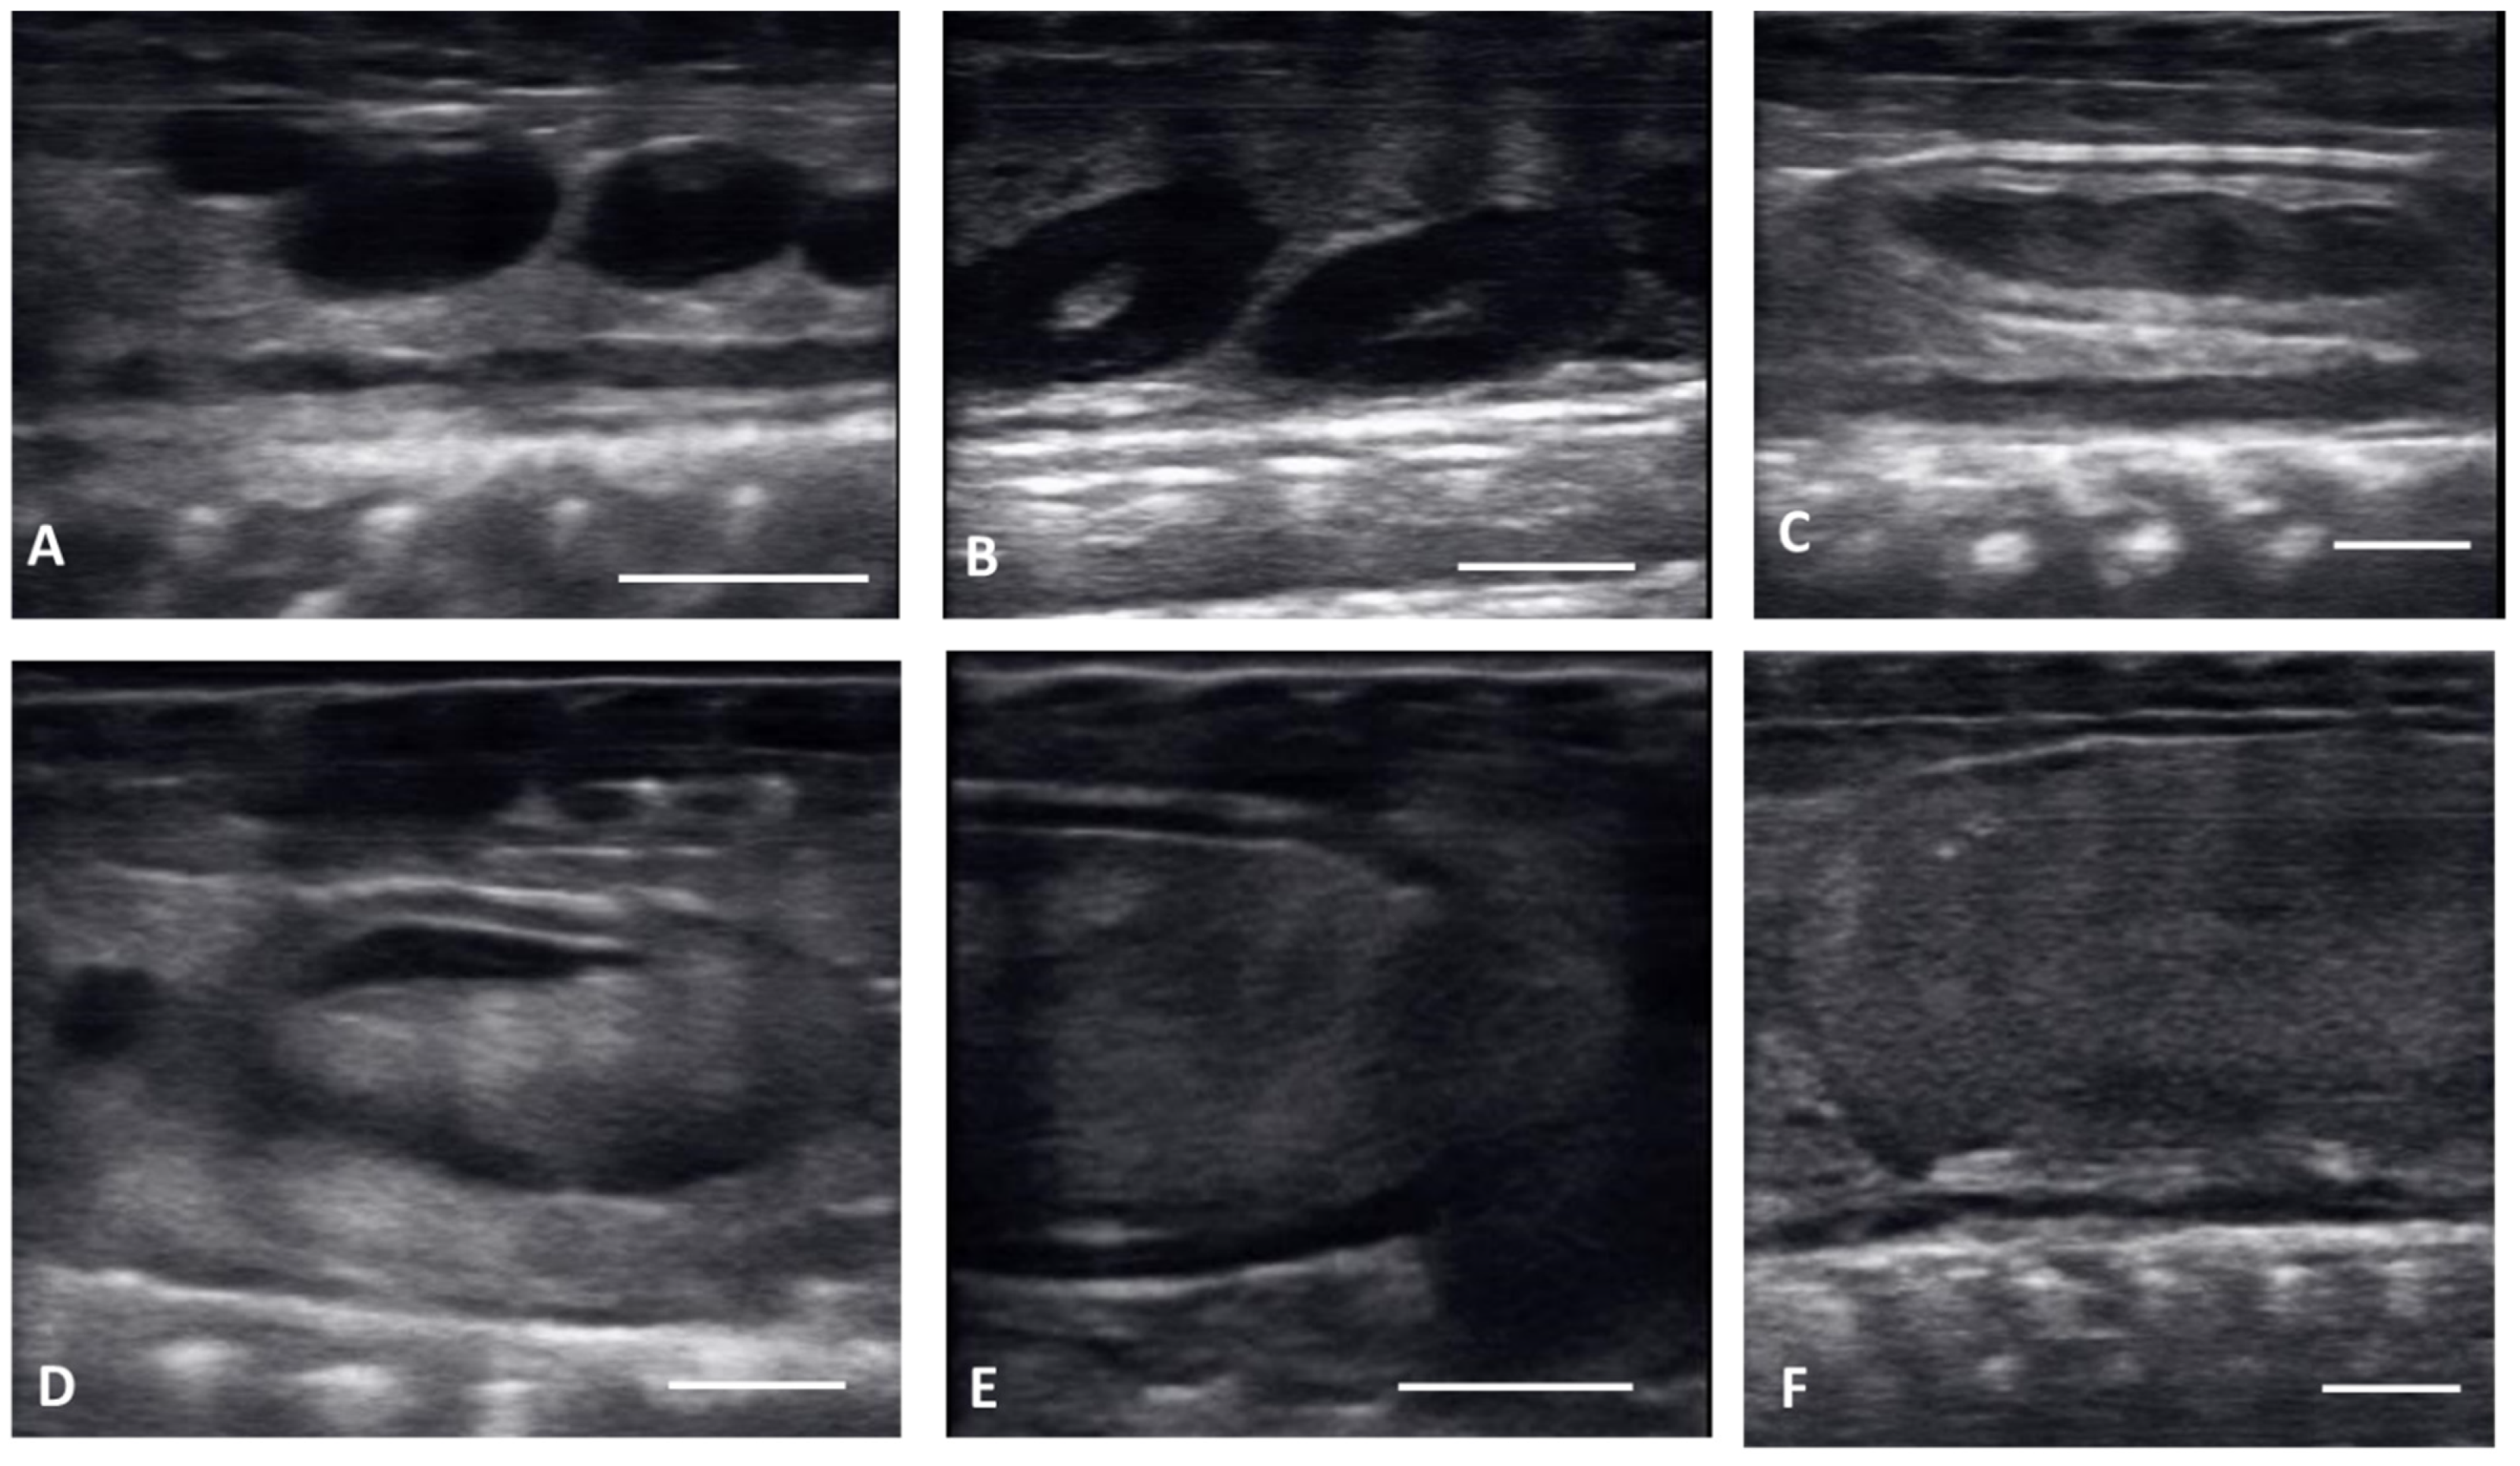

| Previtellogenic Follicles (PVF) | Anechoic Follicles, Small and Rounded, String-Aligned |

|---|---|

| Early vitellogenic follicles (EVF) | Small, round follicles showing hyperechoic outline around an anechoic middle and hyperechoic center. |

| Vitellogenic follicles (VF) | Oval shaped follicles showing a thickening hyperechoic outline as granulosa cell layer increase, hyperechoic ooplasm, and an anechoic core centrally located. |

| Preovulatory follicles (PrOV) | Elongating and increasing hyperechoic ooplasm as follicles are filled with yolk, with an elongated anechoic area located in the periphery of the ooplasm. |

| Peri-ovulatory follicles (PERI) | Elongated follicles, mostly homogenous hyperechoic structure with thick hypoechoic outline. Before female is overtly swollen. |

| Post ovulatory follicles (POV) | Ovulated follicles, passed into the oviduct showing an hypoechoic surrounding, but no visible calcified layer. |

| Shelled eggs (Shell) | Ovulated follicles, passed into the oviduct and surrounded by a calcified layer. |